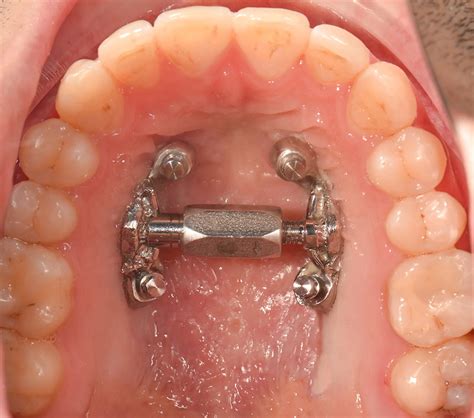

MARPE: Expansión Rápida Asistida por Microimplantes

En los últimos años ha aparecido una innovadora técnica llamada MARPE (Microimplant Assisted Rapid Palatal Expansion), basada en el anclaje de un expansor a través de microtornillos en el paladar. Esta técnica nos permite aplicar las fuerzas necesarias para expandir el maxilar sin tener que aplicar fuerzas en los dientes del paciente. En los casos en que el hueso sea muy duro (hombres mayores de 30 años y mujeres mayores de 40 años), es posible que sea necesario realizar una cirugía complementaria para ayudar al aparato a realizar la expansión.

El tratamiento con MARPE empieza con un análisis del grosor y el tipo de hueso maxilar a través una radiografía ósea en 3D. Si el análisis es favorable para poder aplicar esta técnica, tomaremos unos registros en 3 dimensiones del paladar con nuestro escáner intraoral. Una vez fabricado el aparato, en la consulta se fijará el expansor en el paladar a través del anclaje de los microtornillos guiados según la planificación digital.

Después de la colocación del expansor en el paladar, el propio paciente lo activará todos los días durante un periodo aproximado de entre tres y cuatro semanas y según las recomendaciones del ortodoncista. A medida que se vaya expandiendo el paladar, el paciente irá notando como aparece un hueco pequeño entre sus incisivos centrales superiores (los dos dientes frontales). Tras acabar el tratamiento activo (3 meses), empezaremos con la ortodoncia mediante alineadores transparentes o brackets, con el objetivo de alinear de forma correcta todos los dientes y cerrar el espacio entre los incisivos. El expansor se mantendrá en el paladar durante 9 meses más, tiempo necesario para que se genere nuevo hueso en el espacio creado en el paladar.